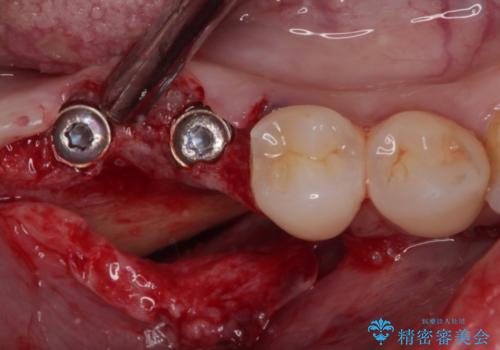

歯の周りの炎症が顕著であったため、抜歯後炎症が治まるのを待ち、咬み合わせが改善できる位置にインプラントを埋入することとしました。

長年の咬合により、周囲の奥歯がすり減っているため、よりインプラントが長い期間安定するよう、睡眠時にはマウスピースを装着することを強く推奨しています。

- 外科手術のため、術後に痛みや腫れ、違和感を伴います